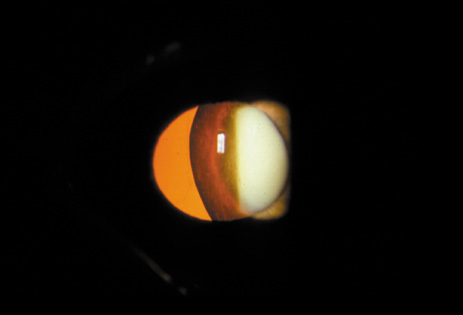

Nuclear cataracts tend to progress slowly. The refractive index of the lens changes as the nucleus progressively hardens, which usually results in increasing myopia.20,21 In some patients this is accompanied by optical distortion, especially of distant images, while near vision remains unaffected. A nuclear cataract is best seen with the narrow-beam direct illumination employed by the slit-lamp, which reveals the color and generalized haze or opalescence of the nucleus. In the early stages, the two halves (cotyledons) of the embryonic nucleus remain visible (Fig. 3). Later the entire nucleus appears as a homogeneous mass in contrast to the cortex (Fig. 4). Retroillumination may show the “oil droplet” effect (Fig. 5). Sometimes one may notice crystals in the lens nucleus (known as a Christmas tree cataract; Fig. 6A and B).

Fig. 5. “Oil droplet” appearance of a pure nuclear cataract seen on retroillumination examination.